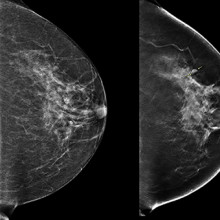

3D imaging technology could improve outcomes for patients with breast cancer

During a conventional digital 2D mammogram, two x-ray images are taken of the breast, one from top-to-bottom and another from side-to-side at an angle. This technology is limited by the overlapping breast tissue that occurs from the required compression of the breast, and breast abnormalities may be hidden. A study at Lawson is looking to determine if digital breast tomosynthesis, a type of 3D imaging, is better at detecting breast tissue abnormalities than the 2D mammography regularly used today. Read more

First Contrast Enhanced Spectral Mammography guided biopsy in North America

Researchers at Lawson performed the first breast biopsy guided by Contrast Enhanced Spectral Mammography (CESM) in North America on June 12, 2020. CESM is a novel diagnostic imaging tool that is able to detect cancerous lesions at a greater rate than standard mammography, and at close rate to MRI. The procedure is faster and more accurate, comfortable and cost effective than an MRI biopsy. Read more.